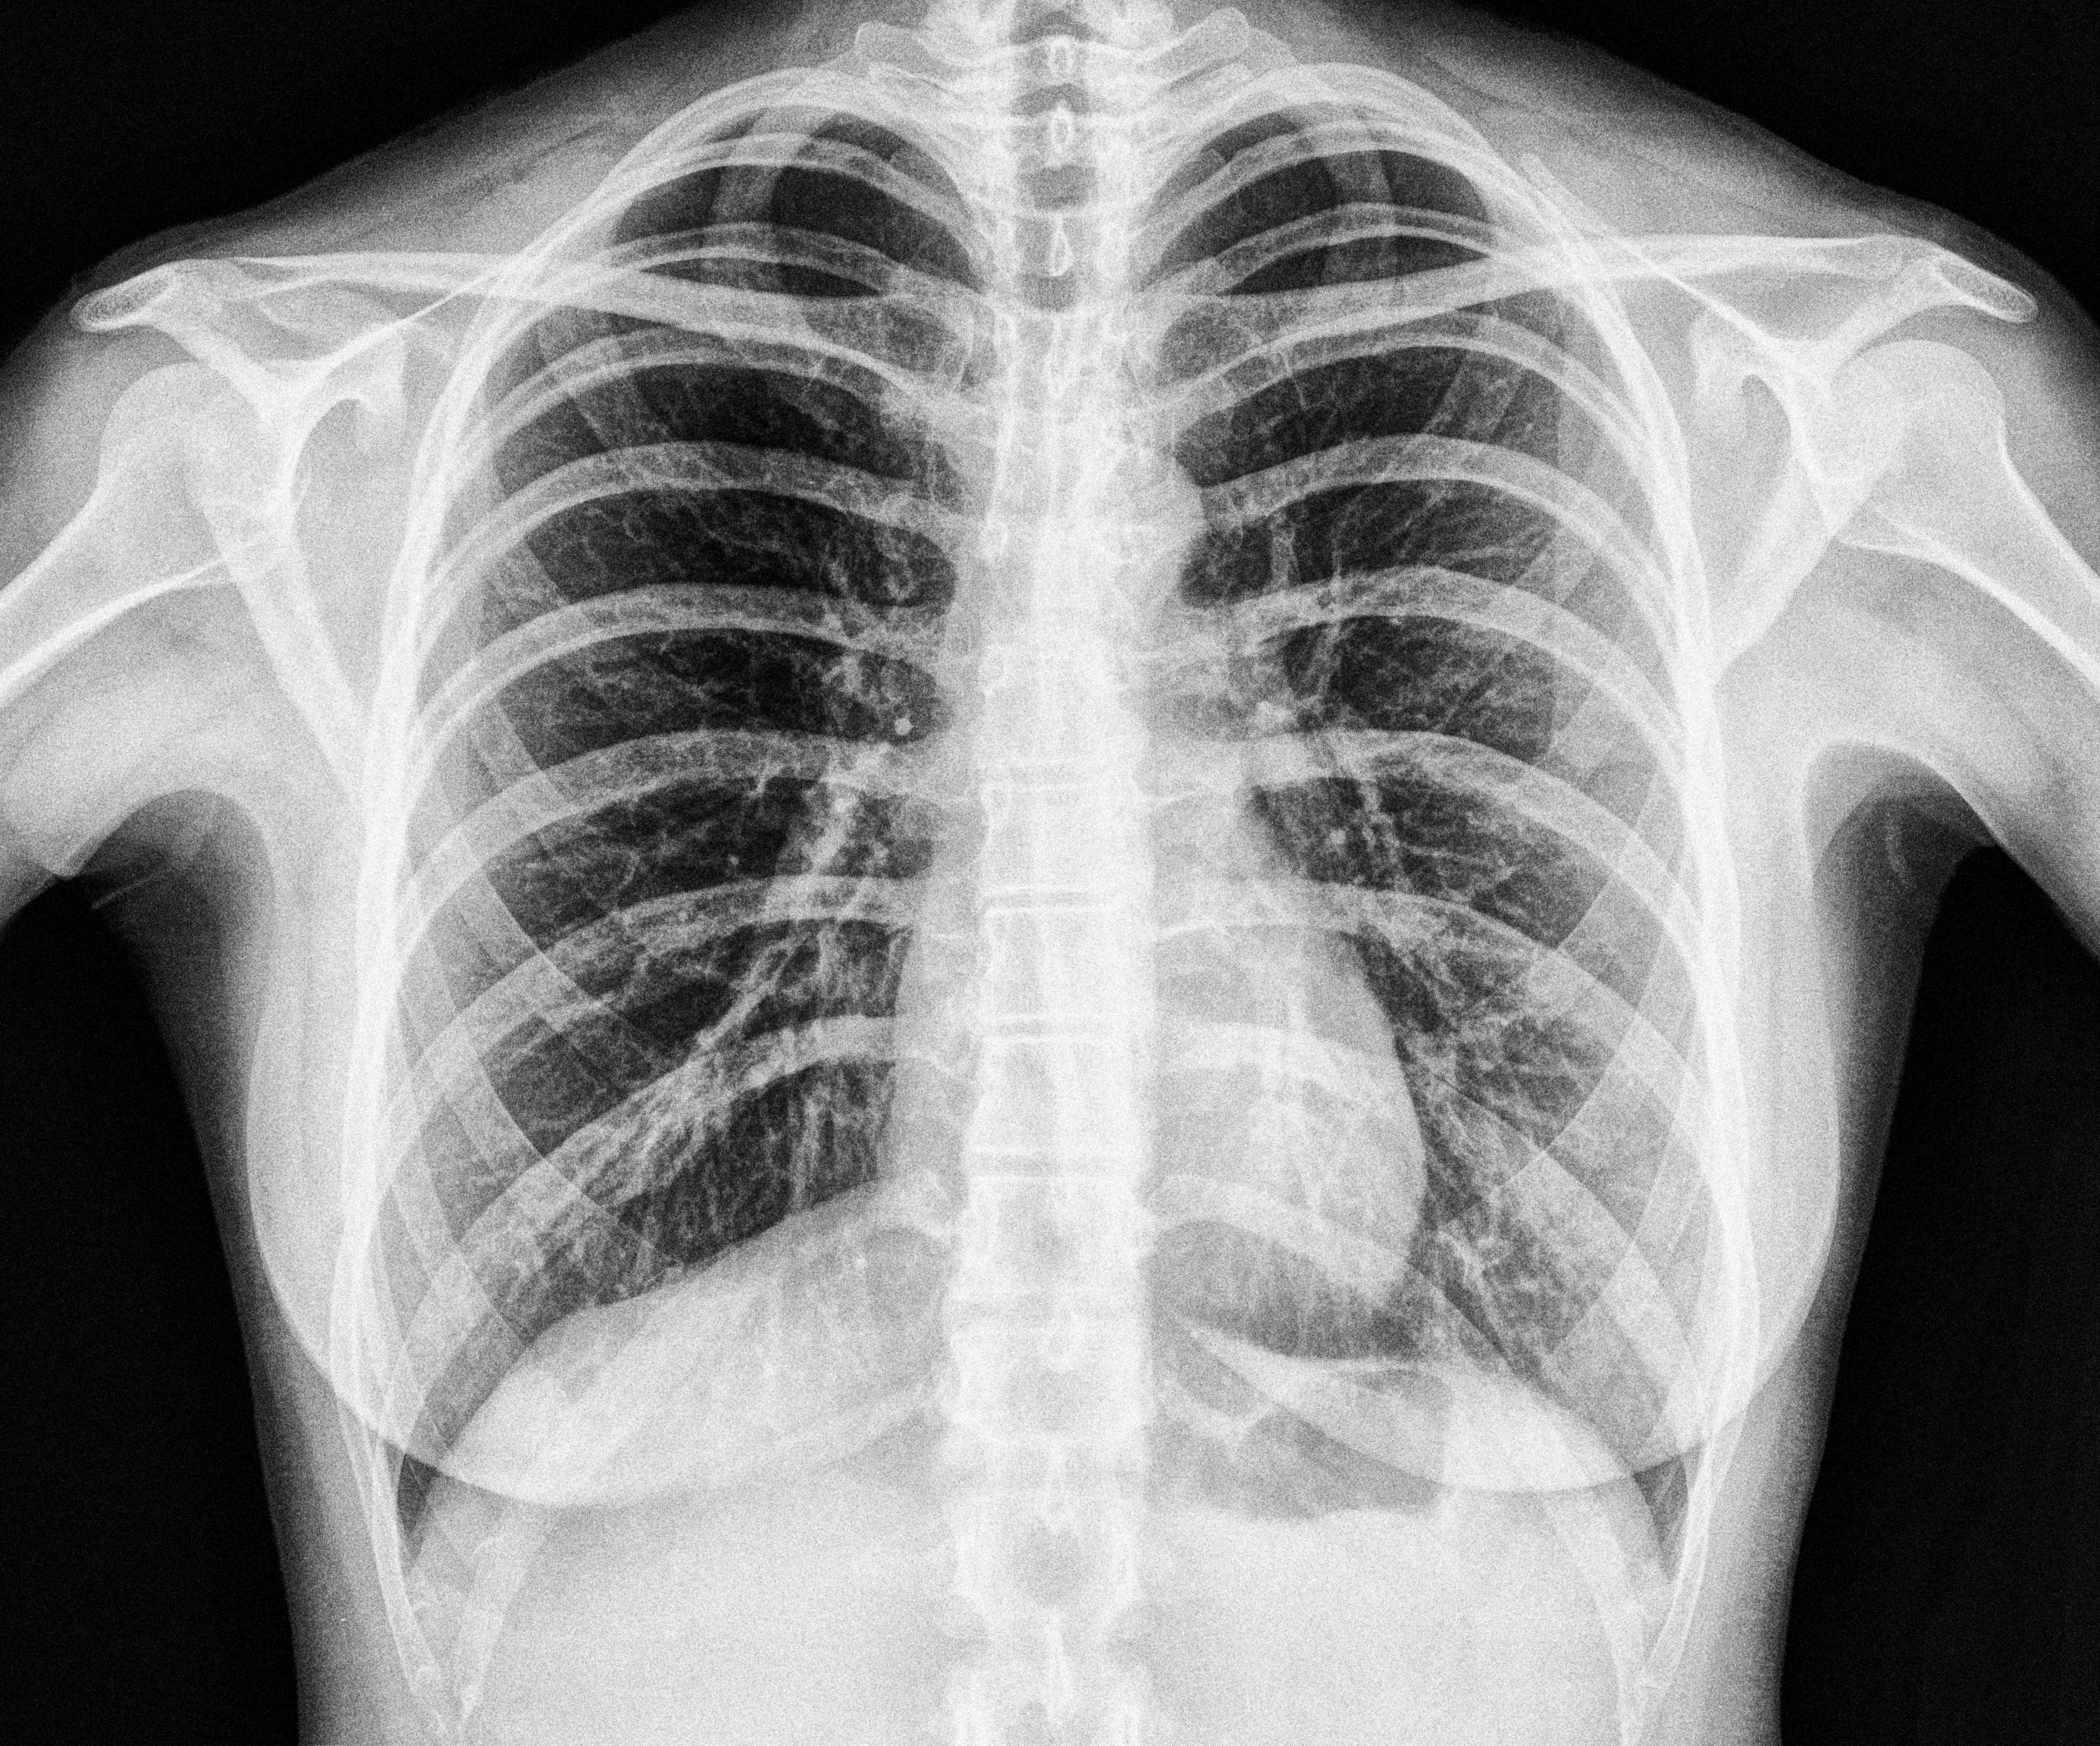

Several Danish hospitals and the American start-up company Enlitic have recently teamed up in a private-public partnership to evaluate an AI-based algorithm in reading chest x-rays. The medical software has been trained on American, Canadian, Japanese and Australian chest radiographs and it is the first time it will be tested and partly implemented in a Nordic country.

The Copenhagen-based hospitals (Herlev/Gentofte, Bispebjerg/Frederiksberg hospitals) and Enlitic have teamed up in a private-public partnership to evaluate an AI-based algorithm in reading chest x-rays. The medical software has been trained on North-American, Japanese and Australian chest radiographs and it is the first time it will be tested in a Nordic country. After the validation process, the algorithm will be implemented in the Nordic setting, for a limited period, to showcase how medical AI will affect the workflow of the Nordic healthcare providers in terms of speed, efficacy and medical decision making.

At the Copenhagen-based hospitals chest radiographs are by far the most frequent images produced in the wards. Since the introduction of digital radiography more than 20 years ago, the appearance of ordinary radiographs of the chest has not changed much and the size and quality of the Danish databases have grown successively. Taken this into account, introducing AI-based software in chest x-rays readings is thus an obvious application area, as AI requires homogeneous training data sets.